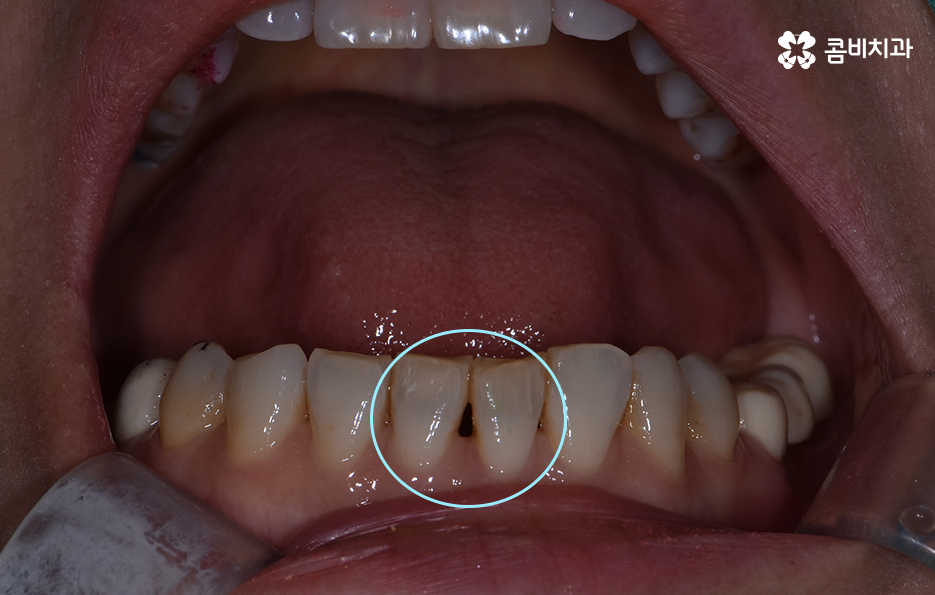

위 환자분의 경우 블랙트라이앵글 레진으로 치료를 하였는데

이러한 레진 치료의 장점은 빠르게 심미성을

회복할 수 있다는 점이며 비교적 저렴하다는 장점이 있습니다.

치아와 치아 사이에 발생한 빈 공간이 주로 삼각형 모양을

띄기 때문에 블랙트라이앵글이라고 부르기도 하는데